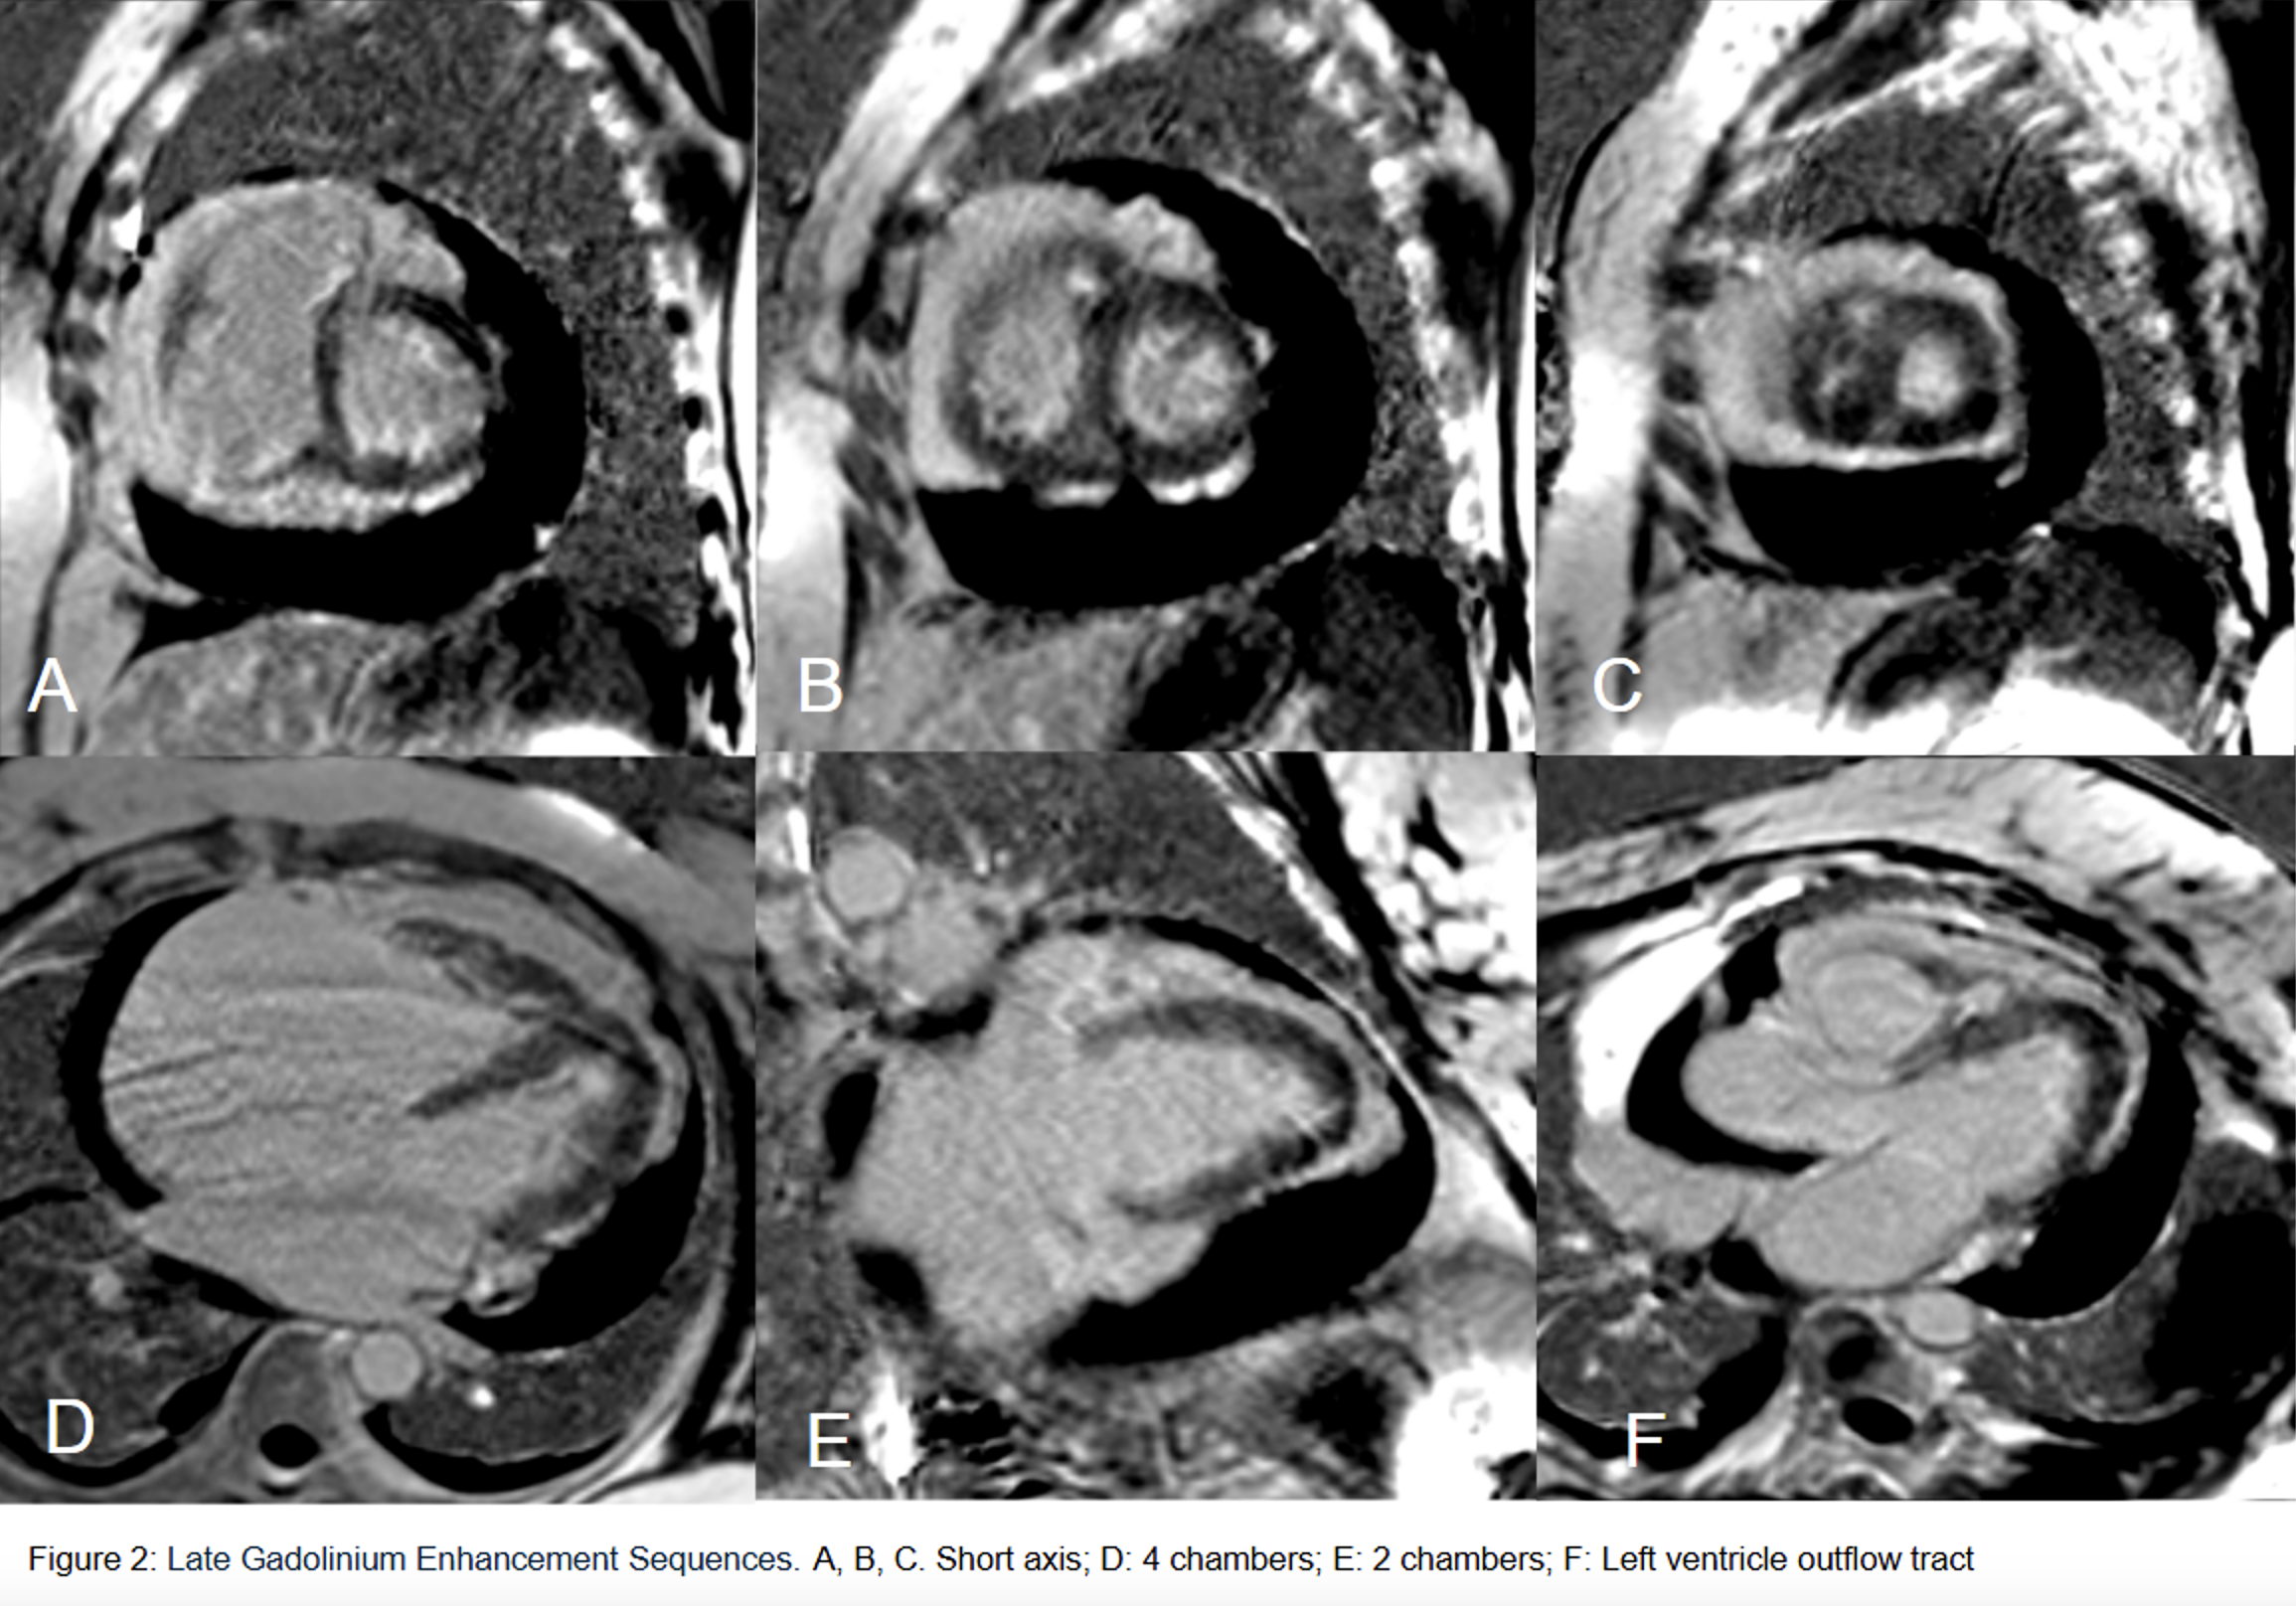

Late Gadolinium Enhancement sequences